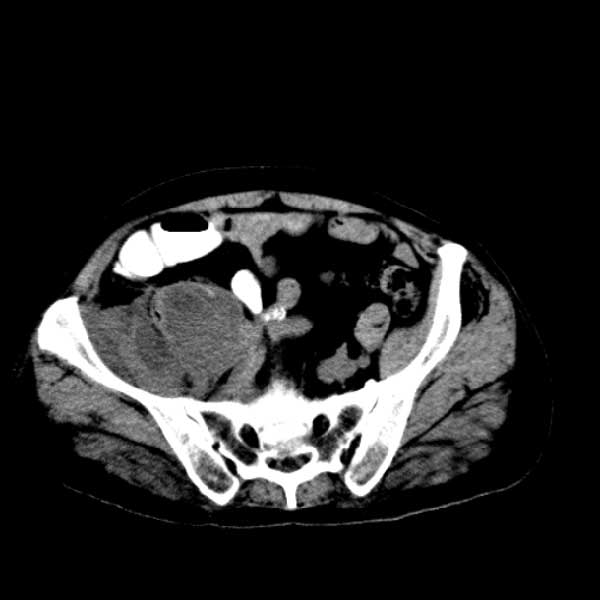

标题: CT13513:男 71 腹部疼痛20余天,近几天高热就诊,骨窗未见异 [打印本页]

标题: CT13513:男 71 腹部疼痛20余天,近几天高热就诊,骨窗未见异

考虑感染性病变可能性大,起源于阑尾?

感染,脓肿形成

考虑为化脓性阑尾炎.脓肿形成.及多肌肉累及.

考虑右侧腰大肌脓肿,向右髂窝、右腹股沟流注。

支持化脓性阑尾炎伴右髂窝脓肿、腰大肌腰方肌脓肿形成。

考虑腹腔及盆腔化脓性炎症,累及右侧髋关节及腹股沟区.

首先考虑化脓性阑尾炎伴腰大肌、腰方肌脓肿,不除外回盲部结核。

回盲部癌待排除。

患者肠镜检查考虑结肠癌,病理证实

患者肠镜检查考虑结肠癌,病理证实。肺部ct可见多发结节,考虑转移